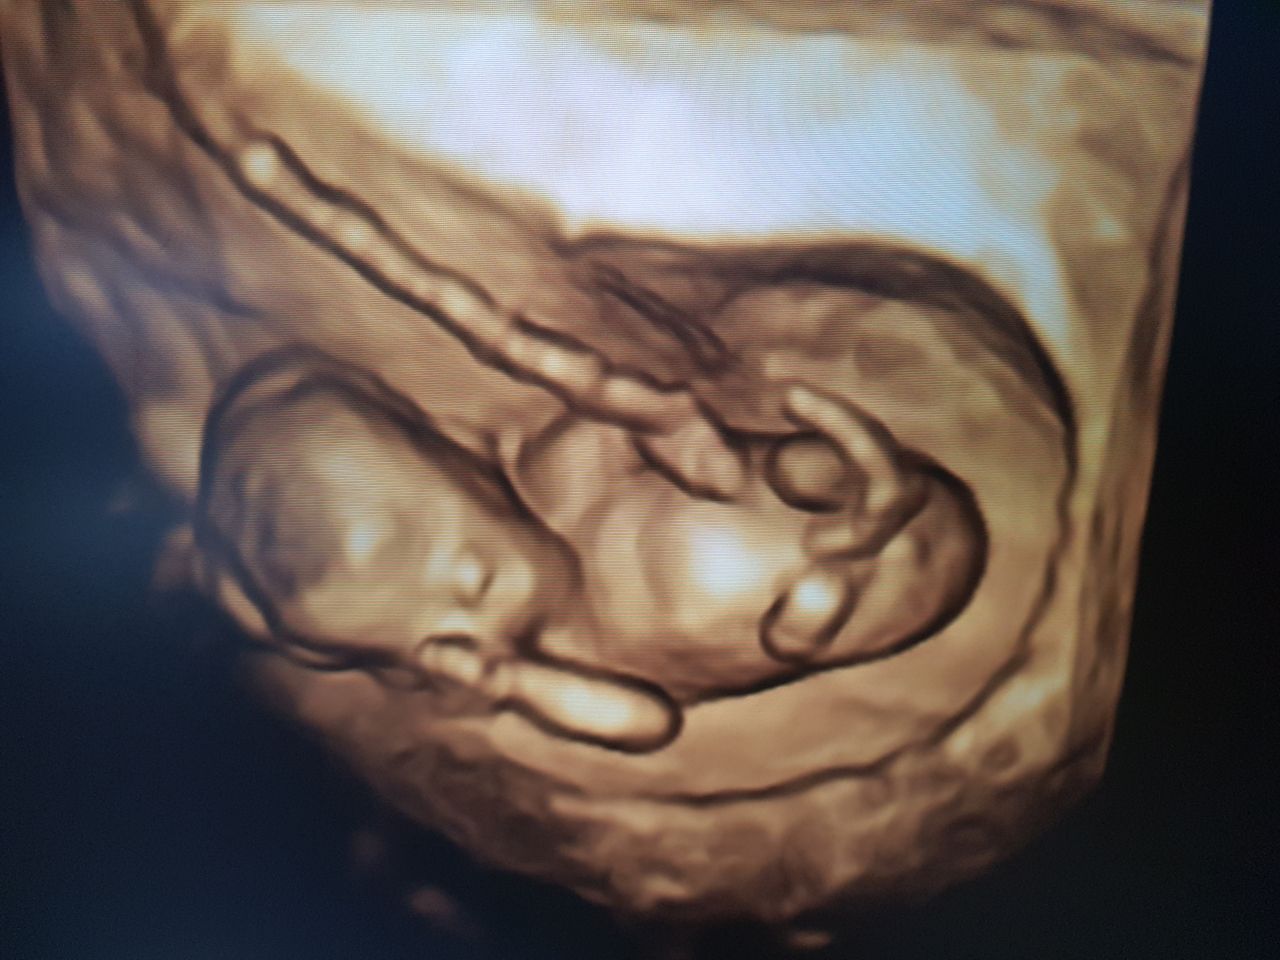

Foto e video